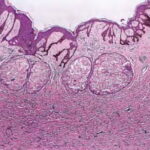

The overlying epidermis is usually acanthotic. Pseudoepitheliomatous hyperplasia and a basaloid proliferation may be noted. The hyperplasia may be caused by the action of fibroblasts on epidermal keratinocytes.23  Basal cell carcinomas occurring upon a dermatofibroma have been reported. Increased pigment may be seen, which may be iron or melanin. Most lesions display a grenz zone of normal papillary dermis overlying the tumor.

The bulk of the tumor is within the mid dermis where no capsule is present and the periphery of the lesion blends with the surrounding tissue. Whorling fascicles of a spindle cell proliferation with excessive collagen deposition are characteristic. At the periphery, the spindle cells characteristically wrap around normal collagen bundles (see the images below). Occasionally, melanocytes have been reported to be interspersed amongst the spindle cells.24